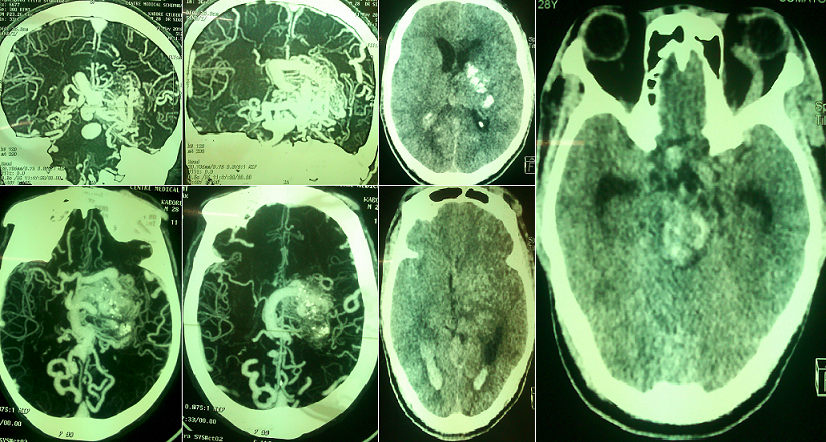

Les malformations vasculaires artériole-veineuses sont des pathologies vasculaires agressives présentant un risque hémorragique lourd de conséquence en termes de morbi-mortalité. Les MAV sont en majorité sporadiques. Le mode de révélation de la MAV est une hémorragie dans 50% des cas. A travers cet article, nous rapportons l'observation clinique d'un patient de 28 ans, hospitalisé dans le service de neurologie du CHU Yalgado Ouédraogo pour déficit moteur de l'hémicorps droit d'installation brutale accompagné de trouble de la conscience. Dans les antécédents, on notait des céphalées chroniques traitées par automédication et des crises épileptiques bravais jacksoniennes droites. L'examen neurologique à l'entrée retrouvait une hémiplégie droite proportionnelle, une aphasie de Broca, une ophtalmologie gauche douloureuse avec ptosis, un chémosis gauche et un syndrome méningé fébrile avec une fièvre à 40°C. Le score NIHSS était à 21/42 et un score ICH à 2 à l'entrée. Le scanner cérébral en urgence montrait une hémorragie cérébrale des noyaux gris centraux et du tronc cérébral, une inondation intra-ventriculaire et des citernes de la base. L'hémogramme notait une hyperleucocytose à 13 200/mm3 à prédominance granulocytaire (72.6%). La radiographie pulmonaire montrait une pneumopathie droite de type alvéolaire. L'intradermo-reaction (IDR) à la tuberculine était positive à 17mm. L'angioscanner cérébrale à distance (J24) retrouvait une malformation arterio-veineuse des artères cérébrales moyennes et vertébrales postérieures et une thrombose du sinus caverneux.